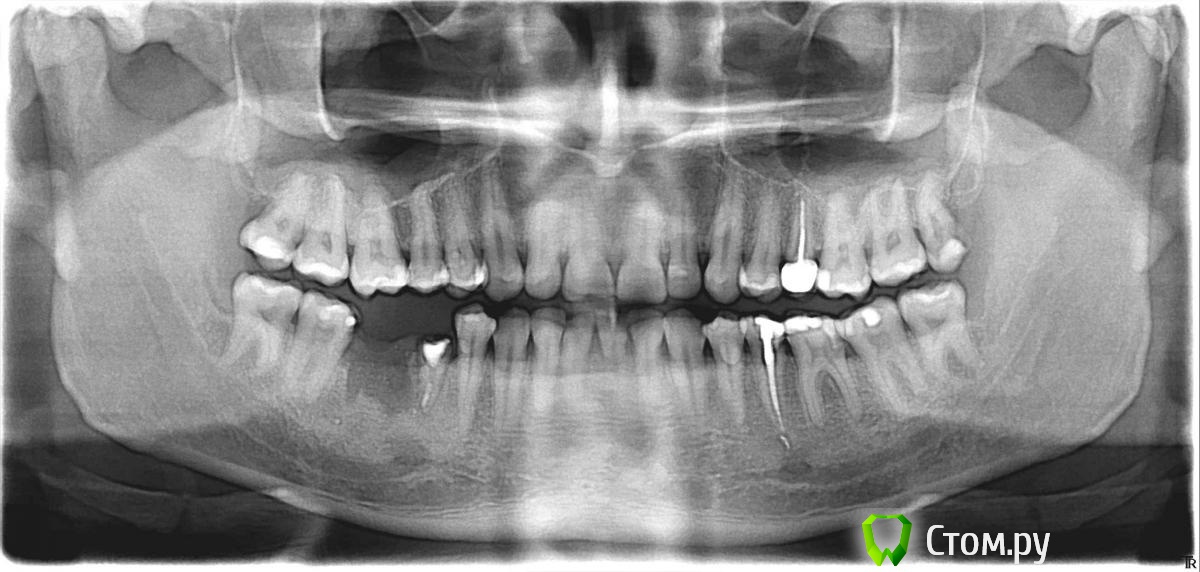

Jenni Опубликовано 21 июля, 2014 Поделиться Опубликовано 21 июля, 2014 Уважаемые доктора. В приложении снимок зубов мужа. Интересует 5 зуб снизу на снимке слева. Несколько дней назад была удалена нижняя 6-ка. Стояли коронка на 5 и 6 зубах. Коронка слетела. зуб 6 восстановление не подлежал и был удален. 5 зуб сейчас под временной пломбой. никаких манипуляций с ним не производилось. Интересует прогноз по этому зубу и если можно. по общей ситуации в полости рта. какие еще есть проблемы.Спасибо. Ссылка на комментарий

Evikrol Опубликовано 21 июля, 2014 Поделиться Опубликовано 21 июля, 2014 45 зуб на удаление, ожидание 3 месяца, повторный снимок, имплантация. Ссылка на комментарий

Бобр Опубликовано 21 июля, 2014 Поделиться Опубликовано 21 июля, 2014 45 - восстановлению не подлежит, удаление Ссылка на комментарий

Evikrol Опубликовано 21 июля, 2014 Поделиться Опубликовано 21 июля, 2014 Очень мало осталось от зуба, крайне тонкие стенки, короткий корень, и он скорей всего зарастает десной. Любая конструкция, если кто то и возьмётся, не простоит и полугода. Даже не мучайте вашего мужа. Ссылка на комментарий

oleg07 Опубликовано 21 июля, 2014 Поделиться Опубликовано 21 июля, 2014 На удаление, хотя если попробовать сделать вкладку возможно простоит годик или меньше, самое оптимальное это удалить Ссылка на комментарий

Evikrol Опубликовано 21 июля, 2014 Поделиться Опубликовано 21 июля, 2014 (изменено) 35 зуб депульпирован, установлен анкерный штифт и пломба на дистальной поверхности. Надо провести осмотр в полости рта, на не состоятельность пломбы на 35, скорей всего необходима коронка на него. А может просто замена пломбы Изменено 21 июля, 2014 пользователем Evikrol Ссылка на комментарий